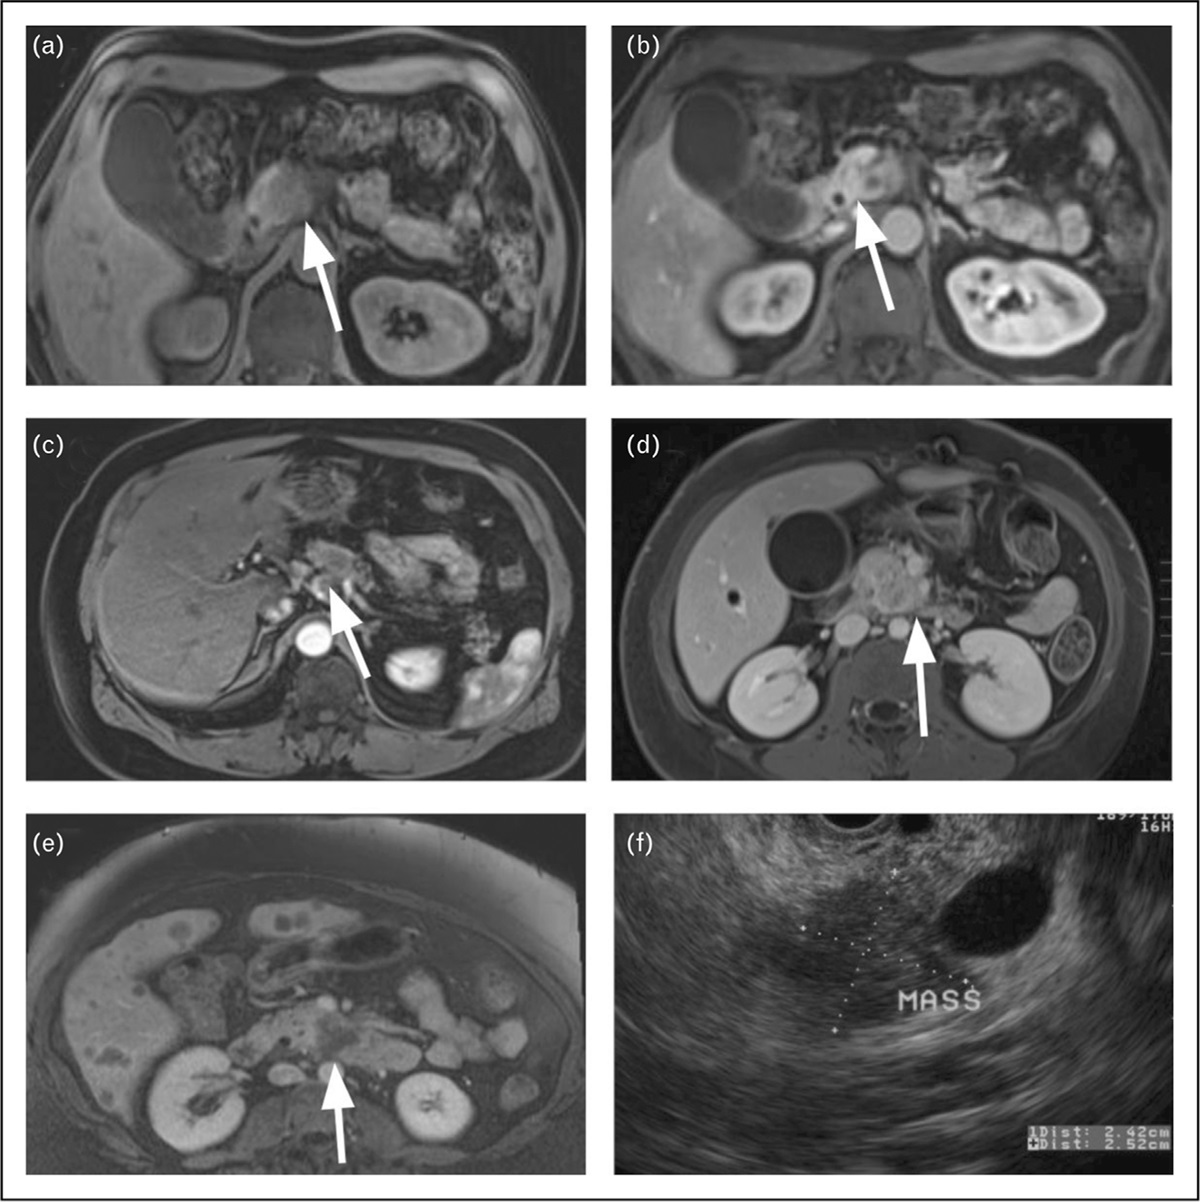

Adenomas are the most common benign lesions of the gastrointestinal tract. The current review aims to summarize recent literature regarding risk factors, natural history, diagnostic and staging technique, and management strategies for ampullary and nonampullary duodenal adenomas.

Surveillance may be a reasonable strategy for sub-centimeter ampullary adenomas occurring in familial adenomatous polyposis, as they carry a relatively low risk of malignancy. Endoscopic resection is the preferred strategy over surgery in patients without lesions suggestive of invasive malignancy. For nonampullary duodenal adenomas, several endoscopic resection techniques are available, each with their unique advantages and trade-offs. In patients who are not operative candidates but have intraductal extension, endoscopic ablation is an emerging option.